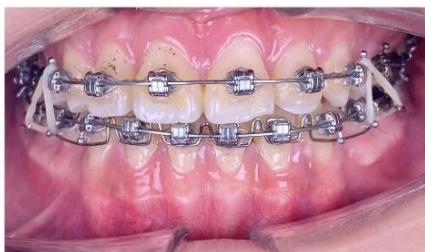

Figure 7: Torque control of the mandibular incisor roots using an ART torque spring during space closure

During canine space closure, a commonly observed side effect is an increased tendency for the roots to approach the cortical bone. At the mandibular canine region (tooth 33), due to the close proximity of

the root to the labial cortical plate, tooth movement was slowed when sliding mechanics were applied [10-12]. Under these circumstances, a single-loop was fabricated on a $0.019 \times 0.025$ -inch TMA archwire to generate a root-directing moment, guiding the root into cancellous bone and thereby "reopening" the biological envelope available for tooth movement. The loop was activated at a rate of approximately $1.5 \mathrm{~mm}$ per month to complete the remaining space closure [19-21].

Following completion of canine space closure, a tendency for maxillary canine extrusion was observed. Therefore, two L-shaped loops with elastomeric elements were applied to deliver an intrusive force, reduce extrusion, and re-establish occlusal plane balance.

Figure 8: Space closure performed by segmented loop mechanics for canine retraction, followed by anterior space closure using a retraction arch with three-dimensional torque control